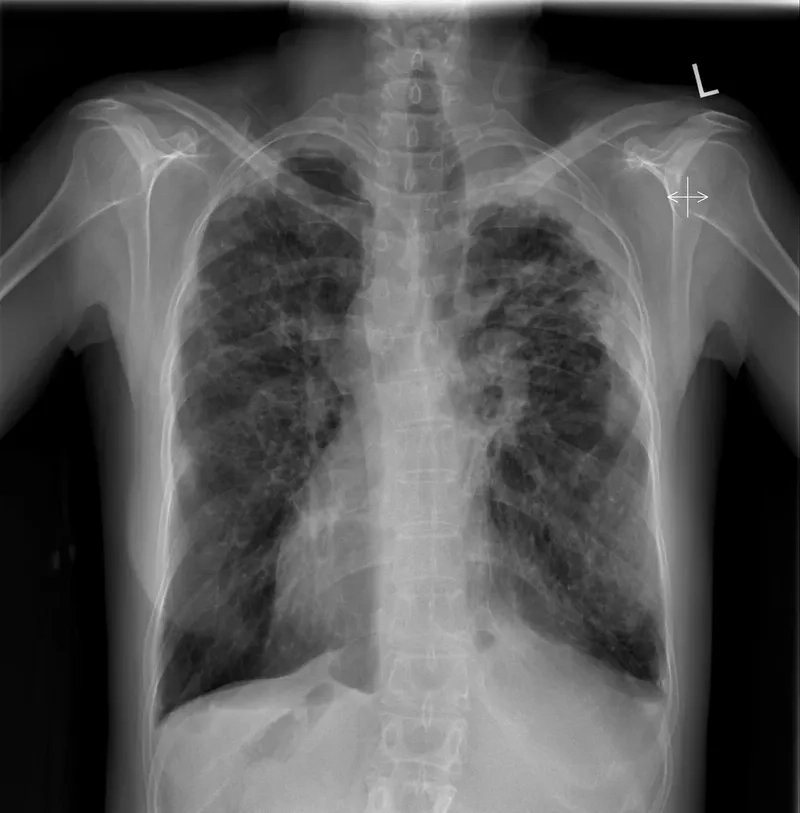

Promoting workplace safety for lung health protection